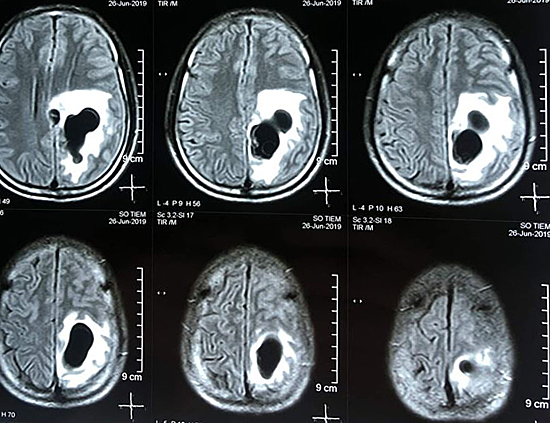

Căn bệnh đầu tiên dễ mắc nhất khi ăn tiết canh là nhiễm ký sinh trùng như sán dây, sán não, giun sán... Trứng giun sán vào trong cơ thể phát triển thành ấu trùng. Ấu trùng sán lợn có khả năng xuyên qua niêm mạc đường tiêu hóa, cư trú ở tất cả các hệ thống từ cơ vân đến cơ tim, cơ hoành, nổi những hạt li ti trên da như con lợn gạo. Ấu trùng sán chui lên não làm tổ, khiến người bệnh có biểu hiện đau đầu, buồn nôn, nôn, có thể có các cơn co giật kiểu động kinh.

Hình ảnh X-quang nhiều ổ sán trên não người đàn ông ở Nghệ An.